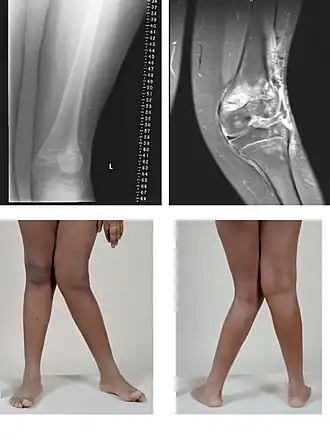

Genua valga

Genua valga of X-benen is een dubbelzijdige naar binnen gerichte buiging van beide benen. De buiging betreft een stand van het onderbeen waarbij dit in de knie ten opzichte van het bovenbeen naar buiten gebogen staat. De rechte lijn, die normaal door de heup, knie en enkelgewricht gaat, valt bij deze aandoening buiten en naast de knie, en ook de binnenenkels raken elkaar niet meer omdat de voeten niet naast elkaar geplaatst kunnen worden. Hierdoor lijkt het alsof beide benen een X vormen.

Er zijn twee soorten X-benen: de slappe X-benen die grotendeels te corrigeren zijn, en de benige verkrommingen. Meestal is er een combinatie van beide. Bij het gefixeerde X-been (benige verkromming) zit de verkromming meestal in het scheenbeen, maar soms ook in het dijbeen en het scheenbeen tezamen. Behalve door stofwisselingsstoornissen en congenitale afwijkingen kunnen X-benen ook veroorzaakt worden door het gebruik van de benen in een buitenwaarts gedraaide stand bij het kruipen. Wanneer de spieren sterk zijn en het skelet zwak ontstaan waarschijnlijk O-benen, terwijl bij een goed skelet en slappe spieren X-benen kunnen ontstaan in deze vroege ontwikkelingsfase.